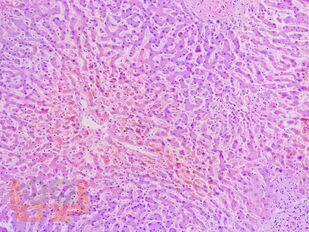

Учебное пособие разработано по дисциплине «Патологическая анатомия - патологическая анатомия головы и шеи» в соответствии с Федеральным государственным образовательным стандартом высшего профессионального образования для студентов, обучающихся по основным образовательным программам высшего образования - программам специалитета по специальности «Стоматология».

В учебном пособии представлен теоретический материал, перечень макропрепаратов и микропрепаратов, демонстрирующих типовые проявления патологических процессов. В цветных иллюстрациях и в описании микропрепаратов сделан акцент на наиболее важных гистологических изменениях, позволяющих на светооптическом уровне диагностировать и дифференцировать состояния, отклоняющиеся от нормы, в том числе с использованием различных гистологических окрасок. Пособие помогает выделить главные аспекты изучаемых патологических процессов, организовать и конкретизировать учебный процесс.